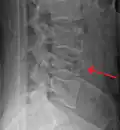

Diagnosis is by medical imaging.

A burst fracture of L4 as seen on plane X ray -